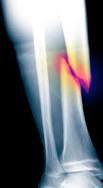

Les auteurs ont voulu savoir si les sites des fractures étaient

différents en fonction de la situation considérée. Il apparaît en

effet qu’avant l’intervention, les sites de fractures sont les

mêmes que chez les patients obèses (plutôt des fractures distales

des membres inférieurs et moins de fractures des membres

supérieurs), alors qu’après l’intervention, les sites fracturaires

deviennent typiquement ceux qui sont constatés dans l’ostéoporose

(membres supérieurs, rachis, col du fémur, bassin).